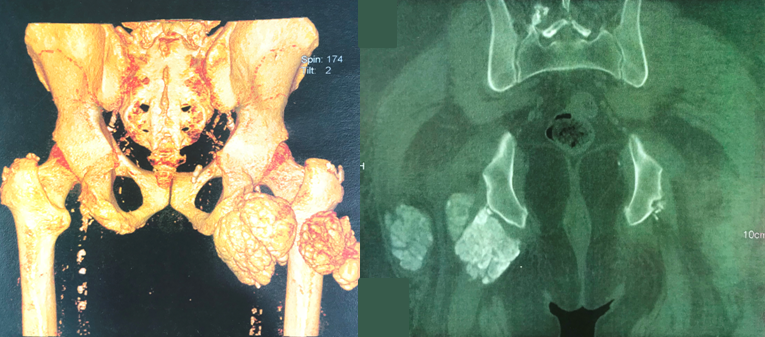

La calcinose pseudotumorale (CPT) est une affection caractérisée par le dépôt de cristaux de phosphate de calcium dans les tissus mous périarticulaires, réalisant de volumineuses masses calcifiées. Bien que la physiopathogénie des CPT ne soit pas totalement élucidée, l'augmentation du produit phosphocalcique au-delà du seuil de précipitation ainsi que l'hyperparathyroïdie sévère, semble y jouer un rôle determinant. Le rôle favorisant de microtraumatismes articulaires répétés est également évoqué. Chez les sujets dialysés, la fréquence de la CPT est estimée entre 0,5 et 7% selon les séries. Son traitement demeure controversé. L'exérèse chirurgicale est souvent recommandée. Nous rapportons un cas de CPT survenue chez un patient hémodialysé. Il s'agit d'un patient âgé de 56 ans, en hémodialyse chronique depuis 9 ans pour une néphropathie indéterminée. Le patient présente depuis 6 mois des douleurs d'aggravation progressive au niveau de la hanche droite, avec des difficultés de mobilisation de l'articulation en regard. Le scanner alors réalisé montre une masse calcifiée, à contours polylobés, mesurant 8,6 x 7,6 x 5,9cm, présentant des rapports très étroits avec le nerf grand sciatique, ce qui explique probablement le tableau clinique très douloureux. Le bilan biologique montre un produit phosphocalcique élevé et une hyperparathyroïdie. L'exérèse chirurgicale est jugée difficile vu les rapports de la tumeur avec les éléments vasculo-nerveux. Notre observation illustre les difficultés diagnostique et thérapeutique de la CPT. L'existence de cette affection peu fréquente nous paraît devoir être rappelée, afin de l'évoquer rapidement chez un patient hémodialysé chronique devant toute masse périarticulaire calcifiée d'allure tumorale.